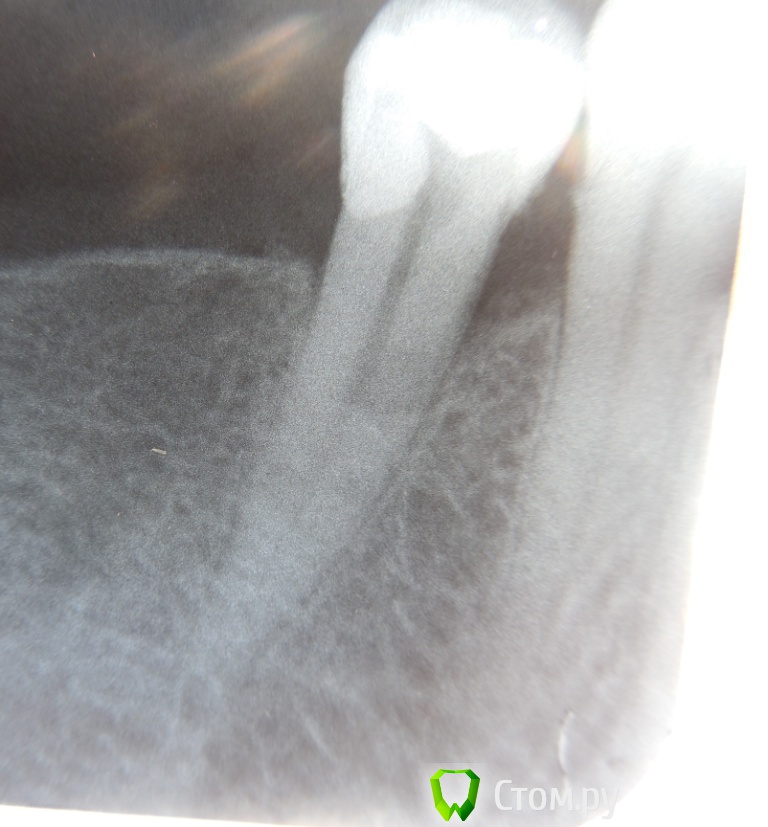

Л-Ф Опубликовано 23 апреля, 2014 Автор Поделиться Опубликовано 23 апреля, 2014 Вот я сделала Контраст снимка в программе и увидала,что плохо запломбировано внизу у корня....... Проверьте,кто-нибудь хорошенько.Боль острая.при смыкании зубов Ссылка на комментарий

Л-Ф Опубликовано 24 апреля, 2014 Автор Поделиться Опубликовано 24 апреля, 2014 Вот пожалуйста,сделала фото корня зуба с Контастом.Тут ясно видно плохое заполнение.Как вы считаете? Жду советы Ссылка на комментарий

red_butler Опубликовано 24 апреля, 2014 Поделиться Опубликовано 24 апреля, 2014 канал нормально запакован Ссылка на комментарий

Гарриевич Опубликовано 24 апреля, 2014 Поделиться Опубликовано 24 апреля, 2014 В пределах канала корня все плотно запломбировано Ссылка на комментарий